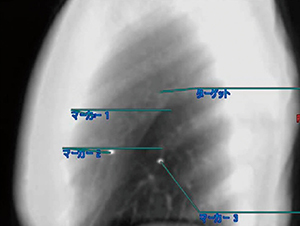

図2は肺がん症例で、標的の周囲に3つの金マーカが留置されているが、動きを視覚的に確認することで、距離の遠近にかかわらず、追跡に最適な金マーカを簡単に判定することができる。

図2 4Dモーション解析を用いた金マーカの指定、距離計測

図6は肺がん症例で、3つの金マーカが留置されており、それぞれの腫瘍との距離がグラフで表示されている。腫瘍とほぼ同じ動きをしているのは赤(マーカ1)であることが一目瞭然である。このグラフは1目盛りが1mmのため、マーカ1の相対的な動きの誤差は±1mmであり、追跡に最適であることが数値で理解できる。

図6 腫瘍と金マーカの距離の評価